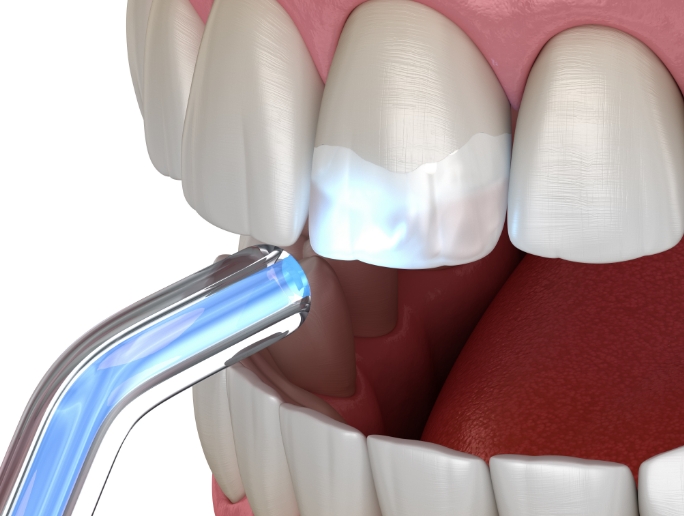

충치를 제거한 만큼의 작은 공간을 레진으로

메우는 방식으로,

치아 삭제 범위가 적고

자연 치아와 비슷한 색을 구현할 수 있어

심미적으로 깔끔한 결과를 얻을 수 있습니다.